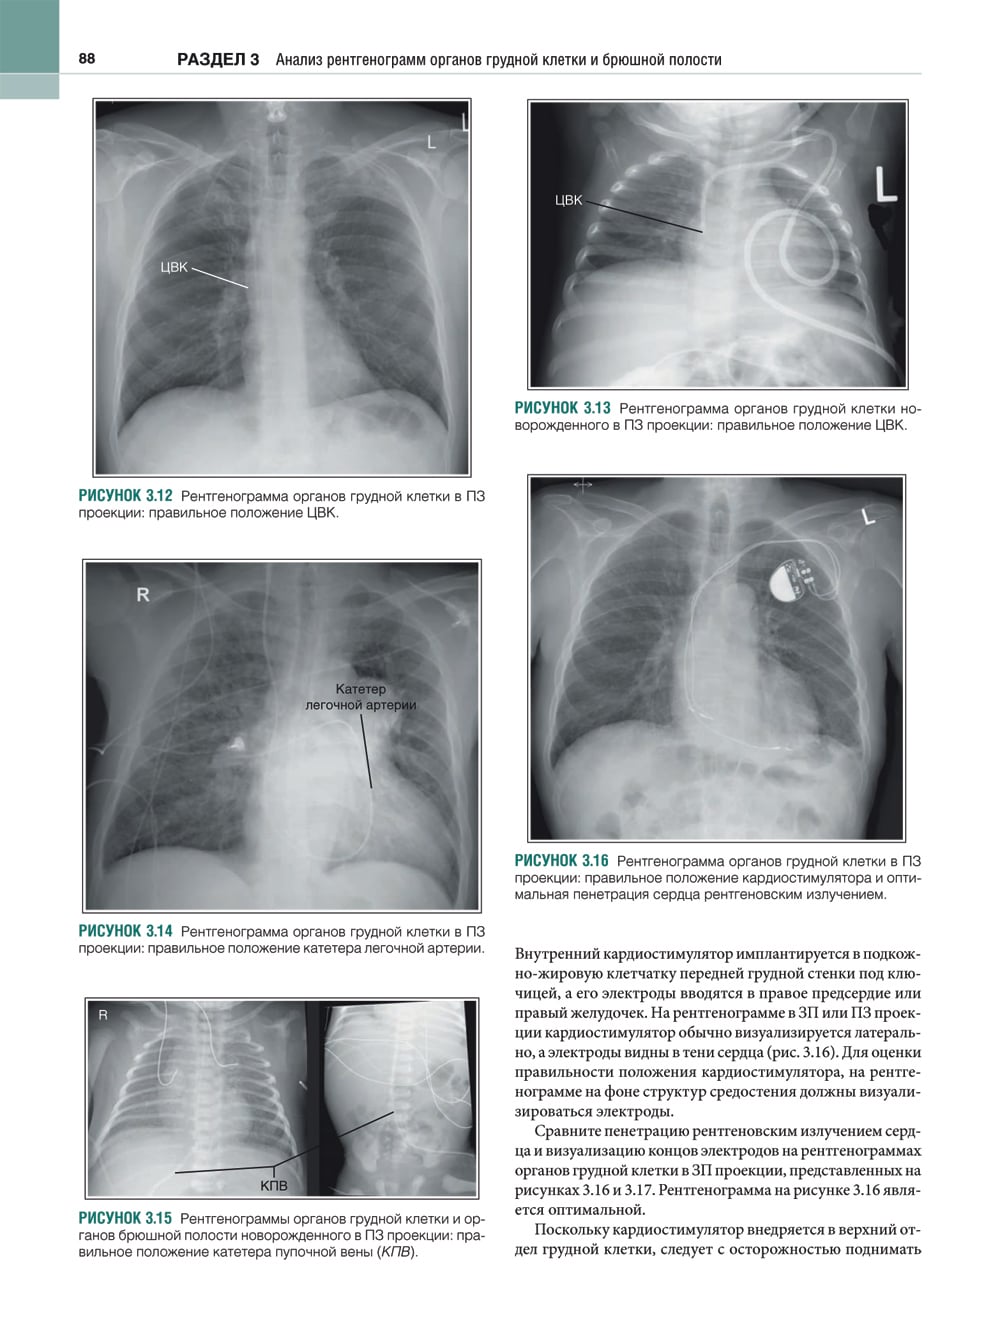

В этом практическом руководстве описаны основные методики выполнения рентгенографии и принципы анализа качества рентгенограмм, стандартные технические параметры исследования, а также варианты укладки и способы их коррекции. Особое внимание уделено базовым принципам получения и цифровой обработки изображений. Для каждой рентгенологической методики приведены фотографии правильной укладки пациента, варианты укладки в нестандартных ситуациях и при определенных патологических состояниях, а также таблицы с сопоставлением вариантов укладки, примеры определения центрального луча или приемника изображения, рисунки и фотографии костных препаратов и условного пациента, позволяющие точнее отобразить взаимное расположение анатомических структур, если проекционное искажение затрудняет интерпретацию рентгенограмм. Издание содержит более 1500 иллюстраций. Книга предназначена для рентгенологов.| Издательство | ИЗД.ПАНФИЛОВА |